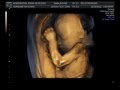

Pittsburgh 3d Ultrasound

Images of Pittsburgh 3d Ultrasound

Pittsburgh 3d Ultrasound Pictures

Photos of Pittsburgh 3d Ultrasound

Pittsburgh 3d Ultrasound Photos

Pittsburgh 3d Ultrasound Images